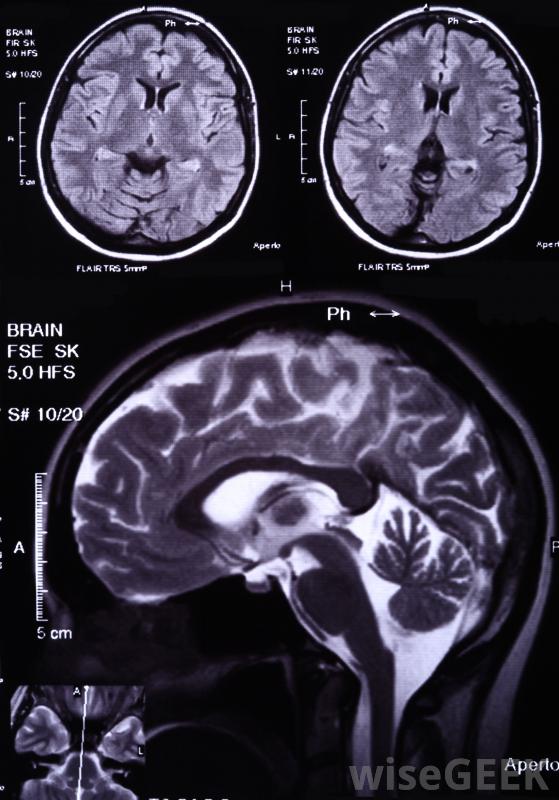

母细胞瘤是起源于胚胎组织的任何肿瘤的总称,因此通常指儿童癌症。母细胞瘤一词通常作为特定肿瘤的医学全称的一部分,如髓母细胞瘤、神经母细胞瘤或胸膜肺母细胞瘤,母细胞瘤的预后或预期的医疗结果会因肿瘤的具体类型和位置而有所不同胚胎瘤这个词出现在各种各样的儿童癌症的医学名称中。胶质母细胞瘤和髓母细胞瘤是指脑瘤。肝母细胞瘤是肝脏的一种肿瘤,肾母细胞瘤是一种影响肾脏的肿瘤。胸膜肺母细胞瘤是一种罕见的影响肺部的癌症。其他常见的儿童癌症包括视网膜母细胞瘤,它影响眼睛;神经母细胞瘤,起源于肾上腺或神经系统的相关部分;以及成骨细胞瘤,母细胞瘤是一种见于骨组织的良性肿瘤髓母细胞瘤是一种儿童肿瘤,起源于小脑,位于大脑下部,可能沿脊柱或特定骨骼转移,这类肿瘤通常可以通过放疗和手术治疗,有时也用辅助化疗,预后很好,胶质瘤和髓母细胞瘤是指脑肿瘤神经母细胞瘤是一种影响肾上腺和神经系统的肿瘤,是儿童和婴儿最常见的非脑源性肿瘤,其症状包括眼周黑眼圈或眼球肿胀,如果肿瘤压迫脊髓,就有可能瘫痪。在大多数情况下,神经母细胞瘤肿瘤在转移后才被诊断出来;这种情况通常在出生时出现,但直到婴儿期或儿童期才被发现

胶质母细胞瘤最常见于45岁至70岁之间的成年人。